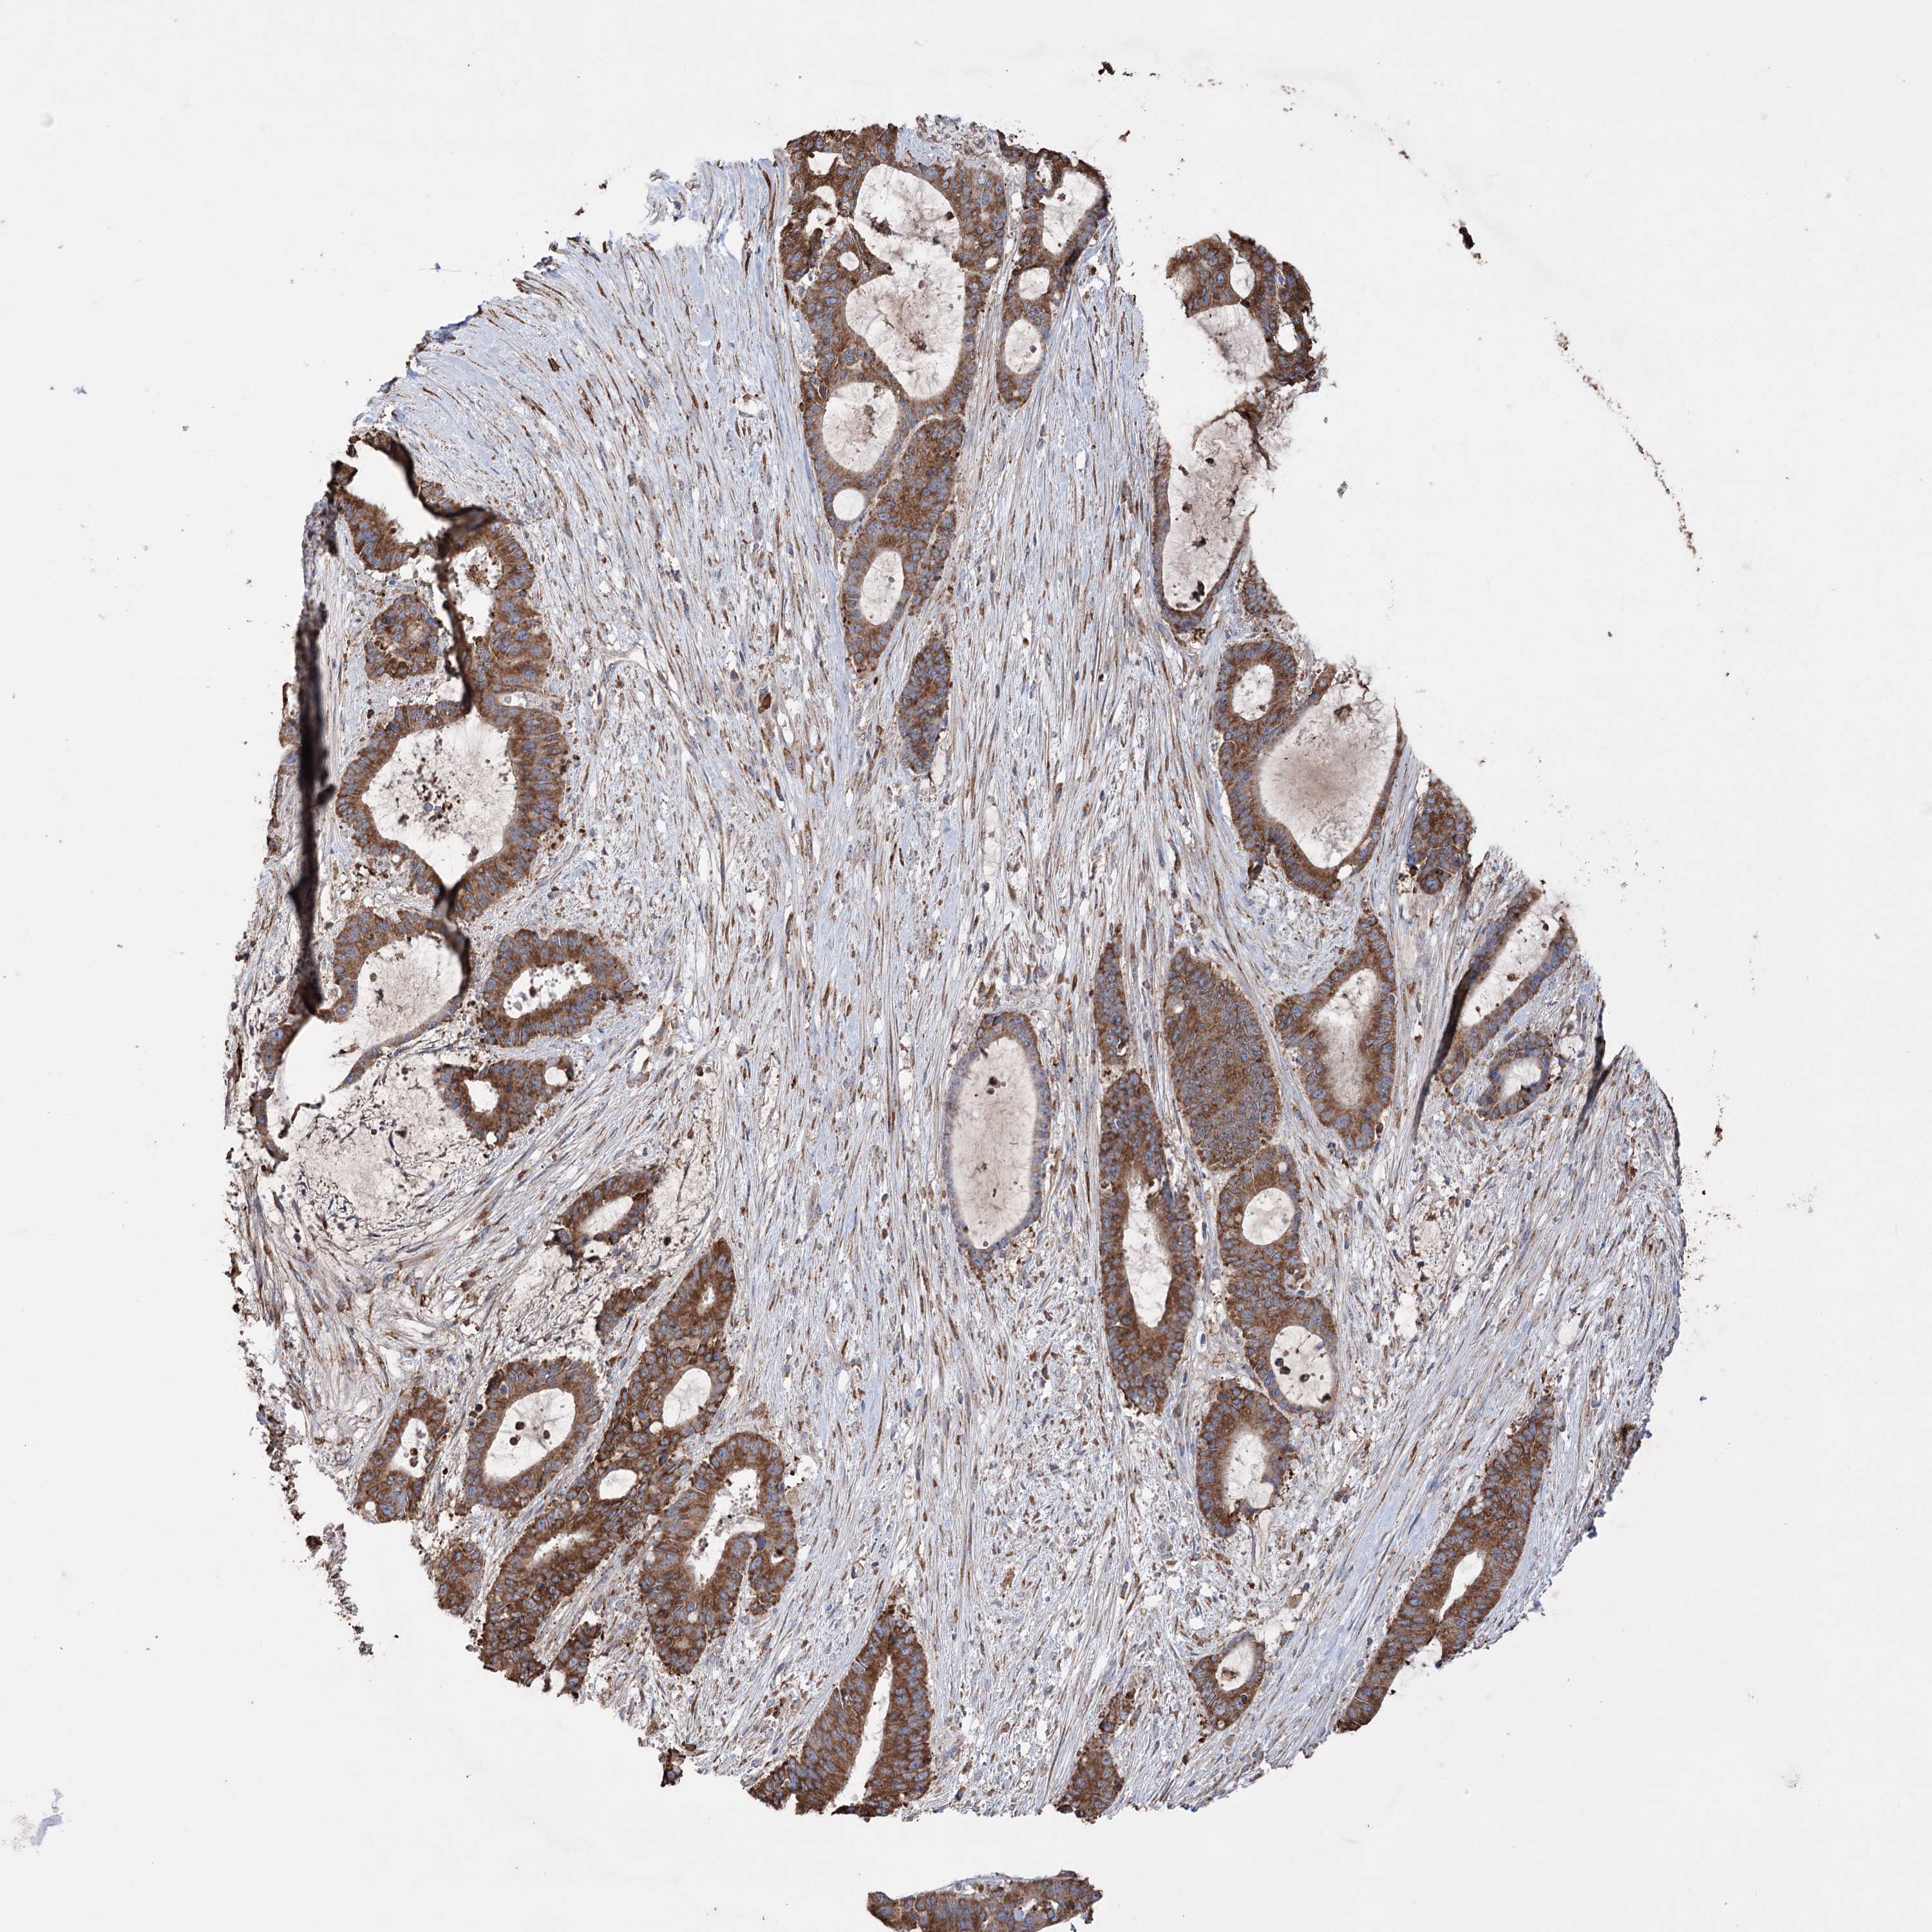

LIVER CANCER - Protein expressioni

A mouse-over function shows sample information and annotation data. Click on an image to view it in a full screen mode. Samples can be filtered based on level of antibody staining by selecting one or several of the following categories: high, medium, low and not detected. The assay and annotation is described here.

Note that samples used for immunohistochemistry by the Human Protein Atlas do not correspond to samples in the TCGA dataset.

Antibody stainingi

Antibody staining in the annotated cell types in the current human tissue is reported as not detected, low, medium, or high, based on conventional immunohistochemistry profiling in selected tissues. This score is based on the combination of the staining intensity and fraction of stained cells.

Each image is clickable and will lead to virtual microscopy that enables deeper exploration of all samples and also displays staining intensity scores, fraction scores and subcellular localization as well as patient and tissue information for each sample.

Antibody HPA038141

Antibody HPA038142

Staining

High

Medium

Low

Not detected

Intensity

Strong

Moderate

Weak

Negative

Quantity

>75%

75%-25%

<25%

None

Location

Nuclear

Cytoplasmic/membranous

Cytoplasmic/membranous,nuclear

Cholangiocarcinoma

Carcinoma, Hepatocellular, NOS